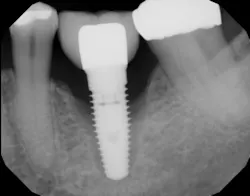

An implant that has lost integration can suffer from fibrous downgrowth (encapsulation) of the entire implant body (figure 1). This tissue acts a barrier to bone-to-implant contact and osseointegration of the replacement implant.6 It is imperative to thoroughly debride the implant socket and meticulously remove all soft tissue prior to implant placement. Proper instrumentation will allow the clinician to reach the apex of the implant socket and be sharp enough to perform curettage on the osseous walls of the socket (figure 2). After complete tissue removal, chemical modification is the next step.

Figure 1: Radiograph showing complete loss of integration and fibrous encapsulation